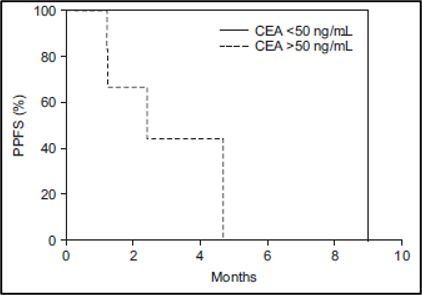

נפח כבד שלם (Whole liver volume) גדול מ-3,000 מ"ל (p = 0.02) (איור 5B), אשר ייצג בעקיפין נפח גידול גרורתי (metastatic tumor volume), היה קשור באופן מובהק להישרדות ללא התקדמות כאב (PPFS) נמוכה יותר. הישרדות ללא התקדמות כאב (PPFS) נוטה להיות גבוהה יותר במטופלים עם קרצינומה נוירואנדוקרינית (neuroendocrine carcinoma) (p = 0.11) (איור משלים 2) ורמה ראשונית של אנטיגן קרצינואמבריוני (CEA) גבוהה מ-50 ננוגרם/מ"ל (p = 0.12) (איור משלים 3). תגובה אובייקטיבית (Objective response) לאחר חודש אחד לא הייתה קשורה להישרדות ללא התקדמות כאב (PPFS) (p =0.43).

איור משלים 3: עקומת ההישרדות של קפלן-מאיר של ההישרדות ללא התקדמות כאב (PPFS) בהתאם לרמה הראשונית של האנטיגן הקרצינואמבריוני (CEA)